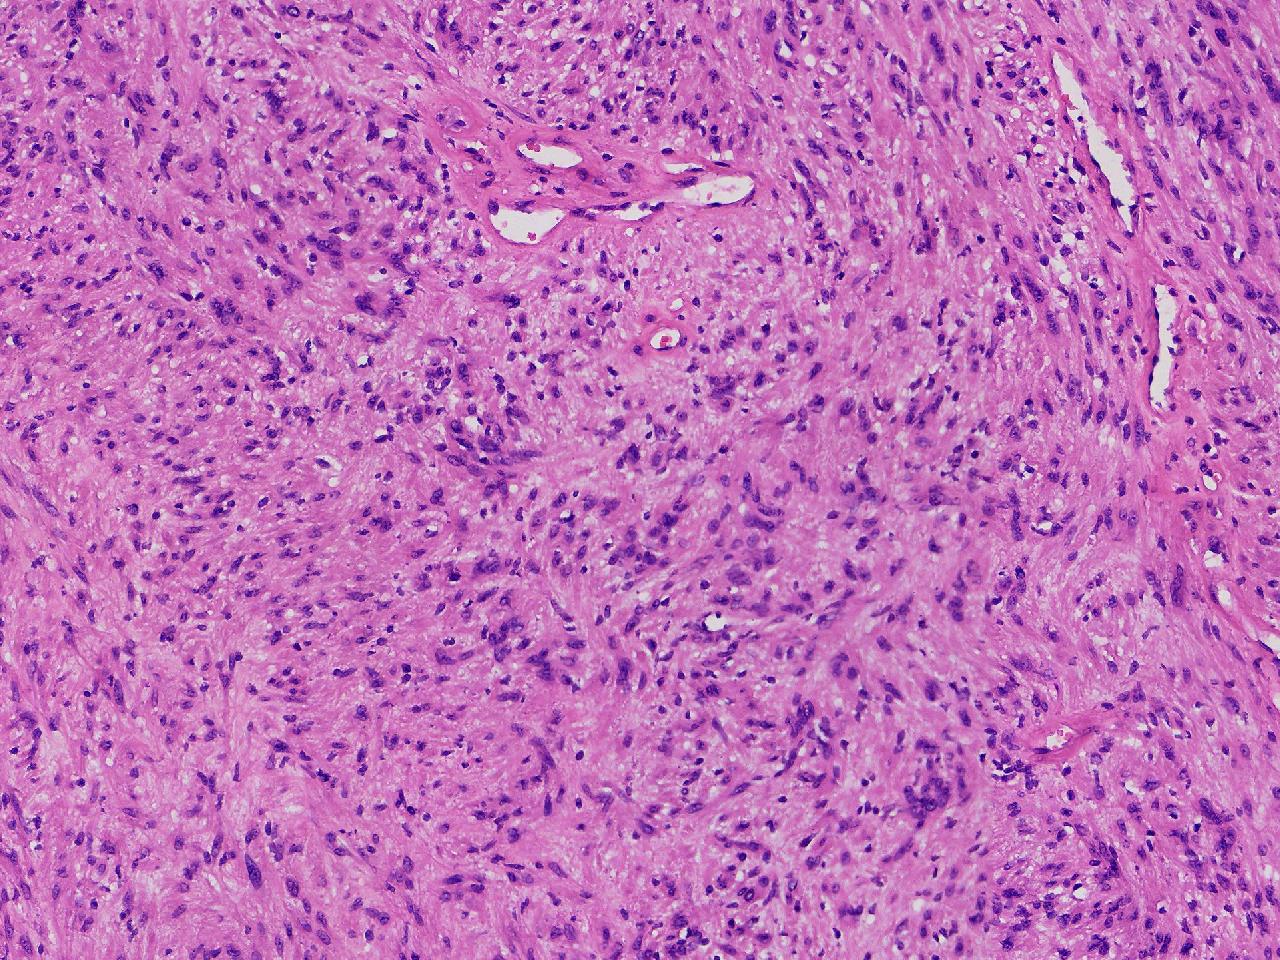

血管平滑肌瘤? 其他?

性别

女

年龄

76岁

临床诊断

右侧腰臀部皮下肿物

一般病史

右侧腰臀部皮下肿物1年余,无明显不适,逐渐增大。

标本名称

大体所见

卵圆形肿物一个,直径1.6厘米,上附皮肤。肿物切面灰黄实性,质中等。

考虑:结节性筋膜炎

神经鞘瘤。

建议除外平滑肌瘤,做IHC是更好的鉴别方式